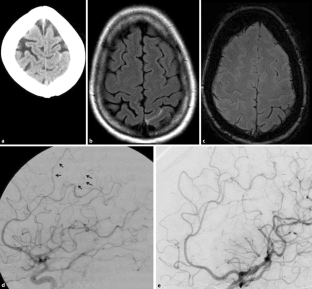

Abb. 3